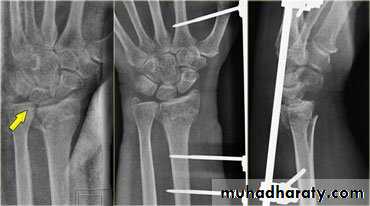

Dr. Saad Abdul AzizColle’s fracture

is a transverse fracture of the distal radius just above the wrist with dorsal displacement of the distal fragment.It’s the most common of all fractures in older people.

fall on outstretched hand, its either undisplaced or displaced .In displaced fracture the distal fragment collapses into extension, dorsal displacement, radial tilt and shortening.

X-rays: AP&Lat. Views

Treatment:

Undisplaced fractureDisplaced fracture: :